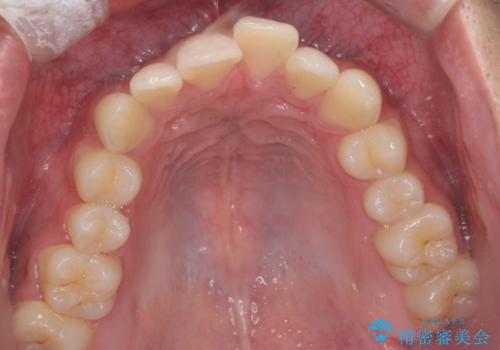

前歯のがたつきを治す治療プランとして

1 矯正を行い歯並びを良くする。(費用と時間がかかる)

2 セラミッククラウンで見た目を良くする(短時間で終わるが歯の向きを無理やり変えるために便宜的に歯の神経を抜く必要がある。健康な歯を削る)

のご提案をしたところ2のプランを選択されたのでセラミック治療を行いました。

- ジルコニアクラウンスペシャル・仮歯 16.5万円×2 精密根管治療(イニシャルトリートメント)・ファイバーコア 8.8万円費用は治療当時の料金となります